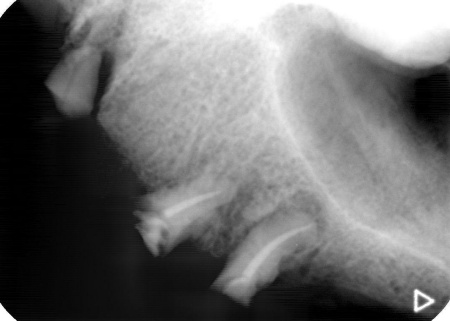

まず、上顎の状態や残存歯について詳しく検査し、温存が難しいと判断した左上の歯3本(犬歯、第1小臼歯、第2小臼歯)を抜きました。

抜歯後は、即時インプラント埋入手術を実施しています。